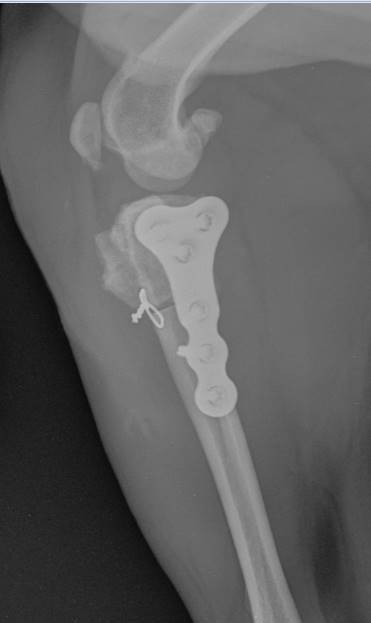

Tibial plateau-leveling osteotomies have become popular techniques for the treatment of canine cranial cruciate ligament disease. This course is designed for the veterinarian who wishes to learn/refine the tibial plateau-leveling osteotomy technique and to understand the major advantages of PAX Polyaxial Locking TPLO Plate System.

Part One of this course is a pre-recorded online lecture that includes a comprehensive discussion aetiopathogenesis, clinical examination, radiographic considerations, TPLO biomechanics, patient selection, complications related to TPLO surgery, pre-surgical planning, instrumentation, surgical technique, and peri/post-operative management.

Part Two of this course is a hands-on workshop. Participants will perform the TPLO technique on a bone model and two canine cadavers under faculty supervision. This lab is only for veterinarians who already have a thorough knowledge of the relevant stifle anatomy, extensive stifle surgery experience, and prior training in bone plating techniques and principles.

This course features two rounds of cadaver work, and each round includes allotted time for pre-op radiographic planning and the instructor’s evaluation of every cadaver’s post-op radiographs. VetRay Technology by Sedecal provides on-site x-ray equipment and support, performing over 150 views at each Securos University 2023 event. They are the world’s largest manufacturer of x-ray equipment and now offer the best selection in digital detector technology. VetRay Technology offers the Digital DX-V which provides HD images within seconds as well as detailed measuring, angle and adjustable circle tools software.